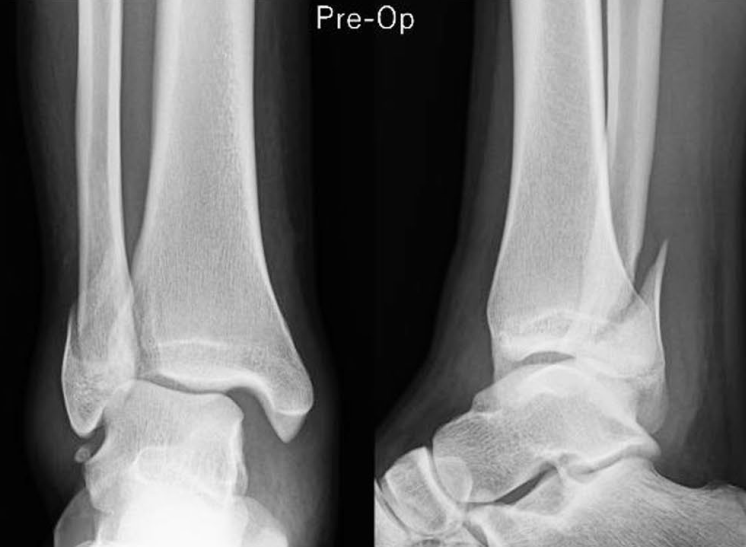

除临时固定外,单纯采用骑缝钉固定外踝骨折,也可避免钢板螺钉的内植物刺激,且在骨折愈合率上不存在劣势: